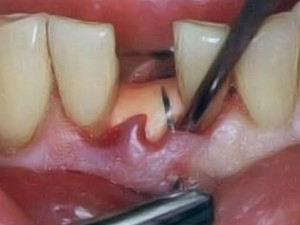

Periodontoloji

Cerrahi Müdahaleler